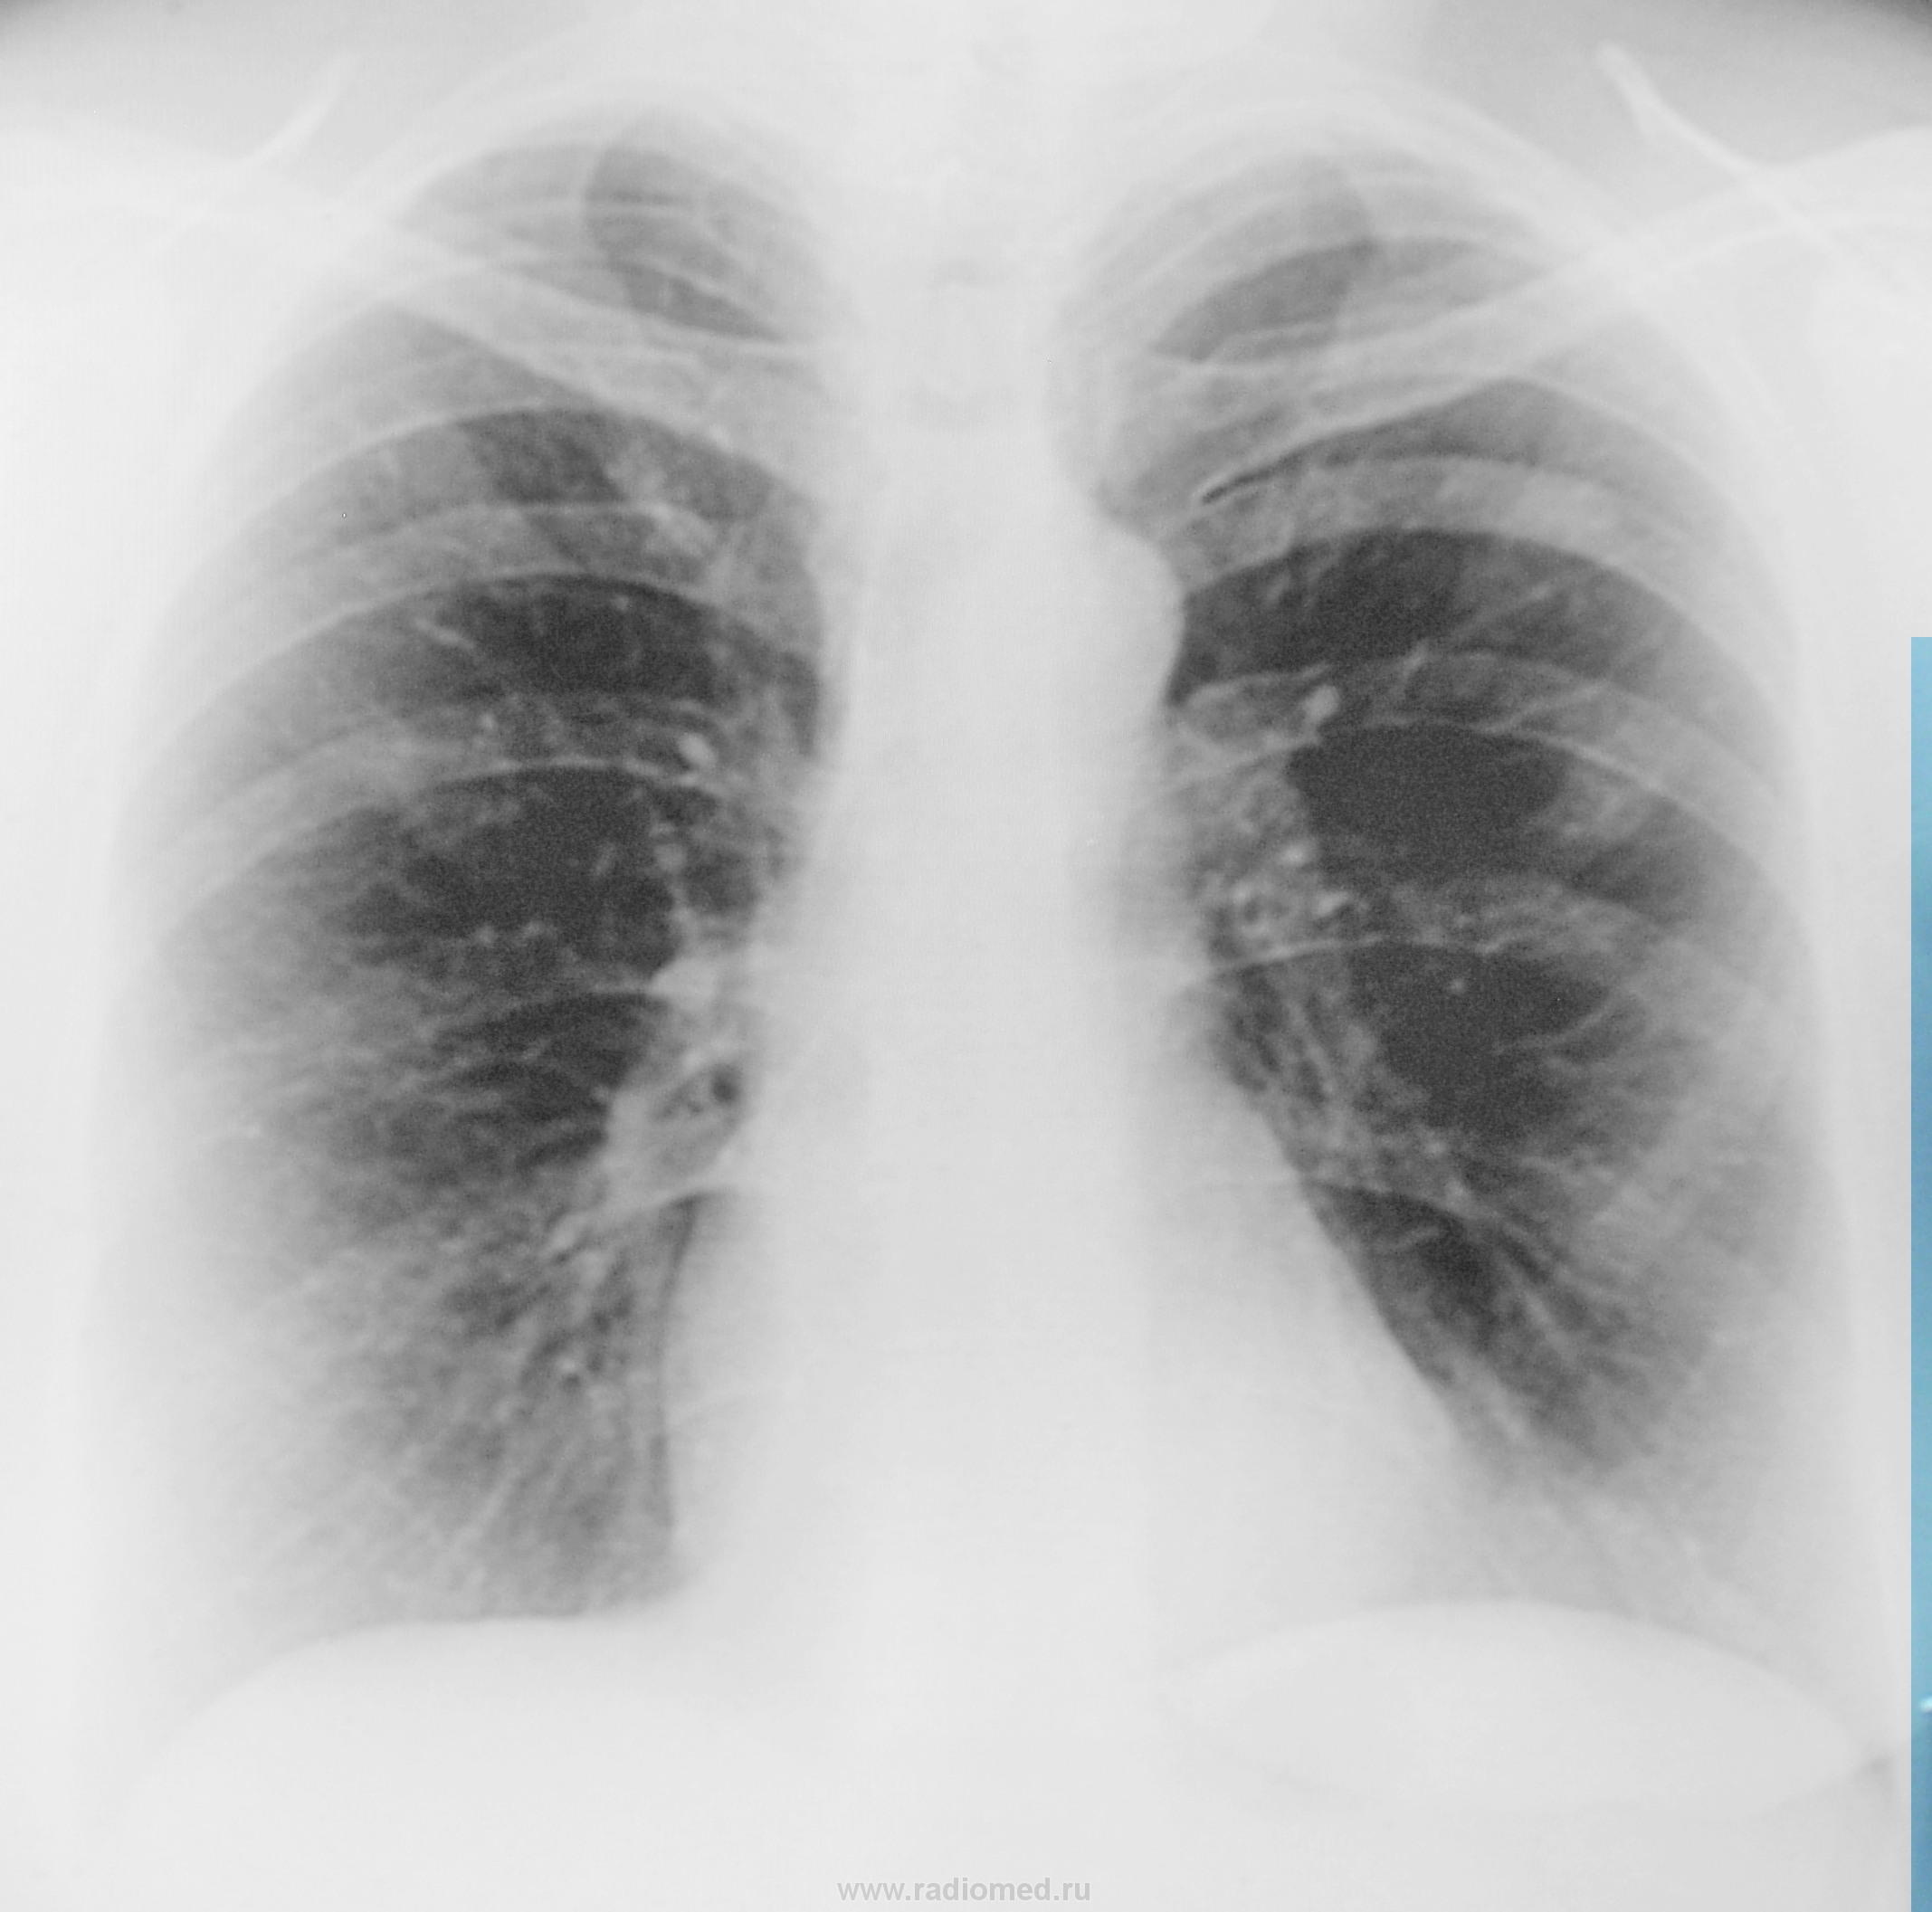

Участок инфильтрата, ввиде дорожки справа в верхней зоне. Ещё насторожила округлая негомогенная тень на интактном лёгочном поле слева в проекции 2 ребра, но точно не уверен.

нужны боковые проекции, желательно с томограммами. А предложил бы ТБС и что-то из периферического (это слева, если там вообще что-то есть?).

Мне наоборот слева явно инфильтрат, а справа-вопрос.

Не знаю. Хотелось бы покрутить, да своим глазом посмотреть. Вроде бы расширение дистального края 3 ребра слева, дополнительно слева в S 2-3 тенюшка. А вот какая? Взять на контроль

первом межреберье слева хорошо видно на флюорограмме. Объясните, что это? См. рисунки, указано стрелками. Nikolas